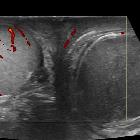

Global

testicular infarction • Whirlpool sign (testicular torsion) - Ganzer Fall bei Radiopaedia